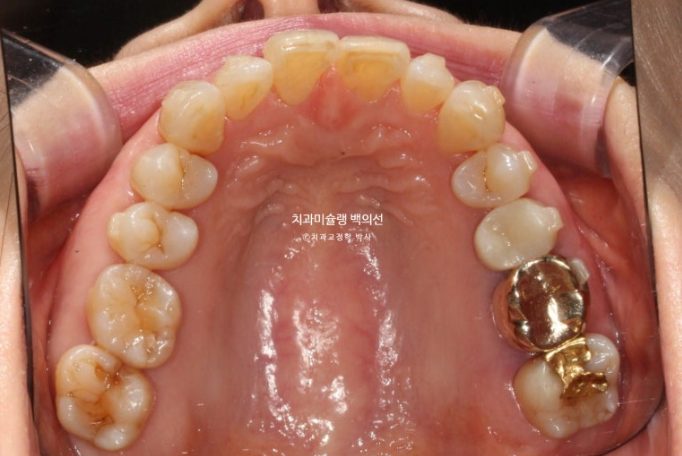

배열은 아주 깔끔합니다.

24.09~25.09

파란 화살표 치아가 치주염이 심해 발치한 치아입니다.

1년간의 교정치료 기간 동안 잇몸뼈는 잘 유지가 되었고 치근평행도는 양호합니다.

개인적으로 안 보이는 부분까지 완벽을 기하기 위해서 치근평행도에 집착하는 편입니다만 아래 앞니 뿌리가 완벽히 평행하지 못한 부분이 조금 아쉽습니다.

파란화살표가 발치한 치아 자리이고 이미 심한 치주염으로 골손실이 심해 인접치아 뿌리가 해당 부위로 충분히 이동해주지 못하기 때문입니다.

뼈가 튼튼해야 그쪽으로 치아이동이 잘 됩니다. 반대로 뼈가 없는 부위로 치아가 이동하진 못합니다.